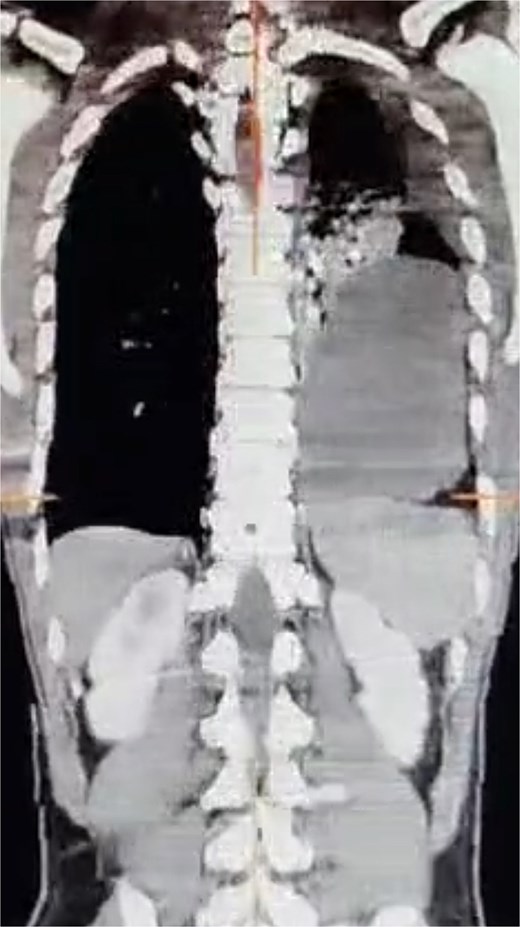

A contrast-enhanced computed tomography (CT) scan revealed an 8 cm posterolateral defect in the left hemidiaphragm with herniation of the splenic flexure and omentum. The herniated bowel appeared viable, with upstream distension and large ascites. A left pleural effusion was also present (Fig. 1).

Contrast-enhanced CT scan showing an 8 cm left posterolateral diaphragmatic defect with herniation of the splenic flexure and omentum into the left thoracic cavity.